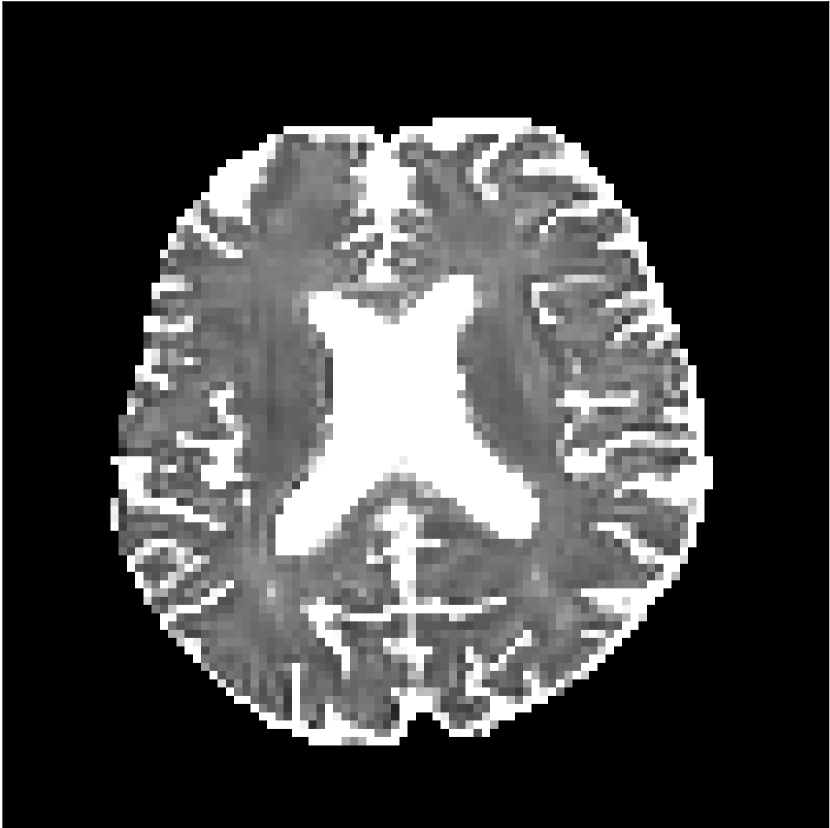

Figure 8 shows examples of non-diffusion-weighted images before and after processing. The raw images (Raw) served as the input for the magnitude deep learning (MCNN) and complex deep learning (CCNN) methods.

Raw 𝐱tsubscript𝐱𝑡\mathbf{x}_{t}

MCNN, fθ^(𝐱t)subscript𝑓^𝜃subscript𝐱𝑡f_{\hat{\theta}}\left(\mathbf{x}_{t}\right)

MCNN Resid., Ric(𝐱t)fθ^(𝐱t)Ricsubscript𝐱𝑡subscript𝑓^𝜃subscript𝐱𝑡\text{Ric}(\mathbf{x}_{t})-f_{\hat{\theta}}\left(\mathbf{x}_{t}\right)

CCNN, fθ^(𝐱t)subscript𝑓^𝜃subscript𝐱𝑡f_{\hat{\theta}}\left(\mathbf{x}_{t}\right)

CCNN Resid., Ric(𝐱t)fθ^(𝐱t)Ricsubscript𝐱𝑡subscript𝑓^𝜃subscript𝐱𝑡\text{Ric}(\mathbf{x}_{t})-f_{\hat{\theta}}\left(\mathbf{x}_{t}\right)

No PF

5/8 PF

Figure 8: Examples of non-diffusion-weighted images from in vivo data at b=0𝑏0b=0 s/mm2. Artifacts in the Raw image, 𝐱tsubscript𝐱𝑡\mathbf{x}_{t}, are corrected by the MCNN and CCNN models, fθ^(𝐱t)subscript𝑓^𝜃subscript𝐱𝑡f_{\hat{\theta}}(\mathbf{x}_{t}). Also shown are the residuals between the CNN corrections and the original Raw image with Rician bias correction Ric(𝐱t)Ricsubscript𝐱𝑡\text{Ric}(\mathbf{x}_{t}) [10]. The Gibbs artifacts removed by the methods are observed in the residuals. The MCNN method introduces some banding artifacts at the PF 5/8ths factor that are not present in the CCNN method.

Both methods remove artifacts, but the MCNN method allows residual rippling artifacts to pass through in the presence of partial Fourier. These rippling artifacts are not present in the CCNN method.